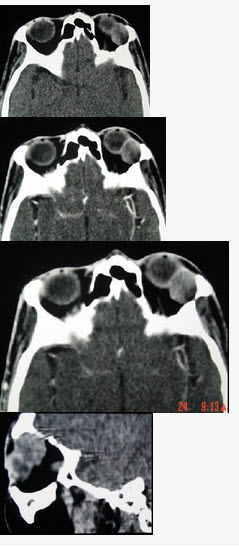

女,36岁,左眼眶外上部可触及一无痛性包块有两年,眼球向内下方突出,CT检查如图,最可能诊断为()

A:泪腺良性混合瘤

B:泪腺恶性上皮性肿瘤

C:炎性假瘤

D:淋巴瘤

E:淋巴瘤样增生